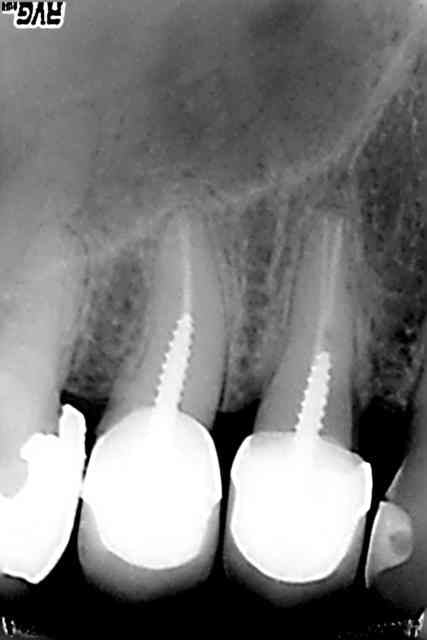

Sx protaper, largo numero 3, re sx pour se rapprocher de l'apex puis s1, s2, f1 f2 protapers. Depuis 4 mois j'ai remplacé s2, f1 f2 par r25 réciproc voir r40.

Ce matin finition r40, pas d'empreinte pour ic, je ne disposais que d'une demi-heure et devis non établi.

Fuck j'arrive pas à virer la radio avec l'inlay core.

J'aime bien le IC sur la pré-molaire

1. c'est une 6, 2. c'est pas une de mes réalisations et ça a au moins 12 ans, comme quoi !